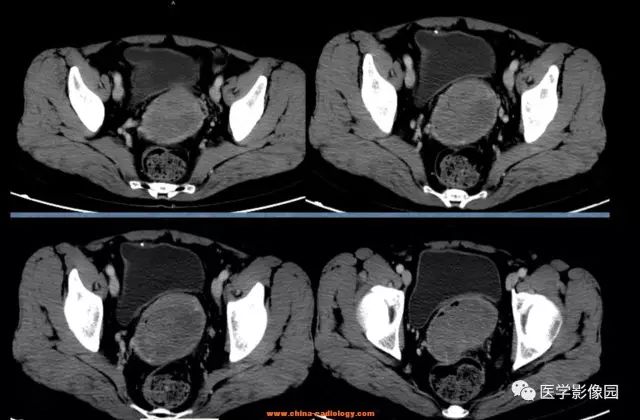

【病例】宫颈癌1例CT影像表现

诊断结果:宫颈鳞癌